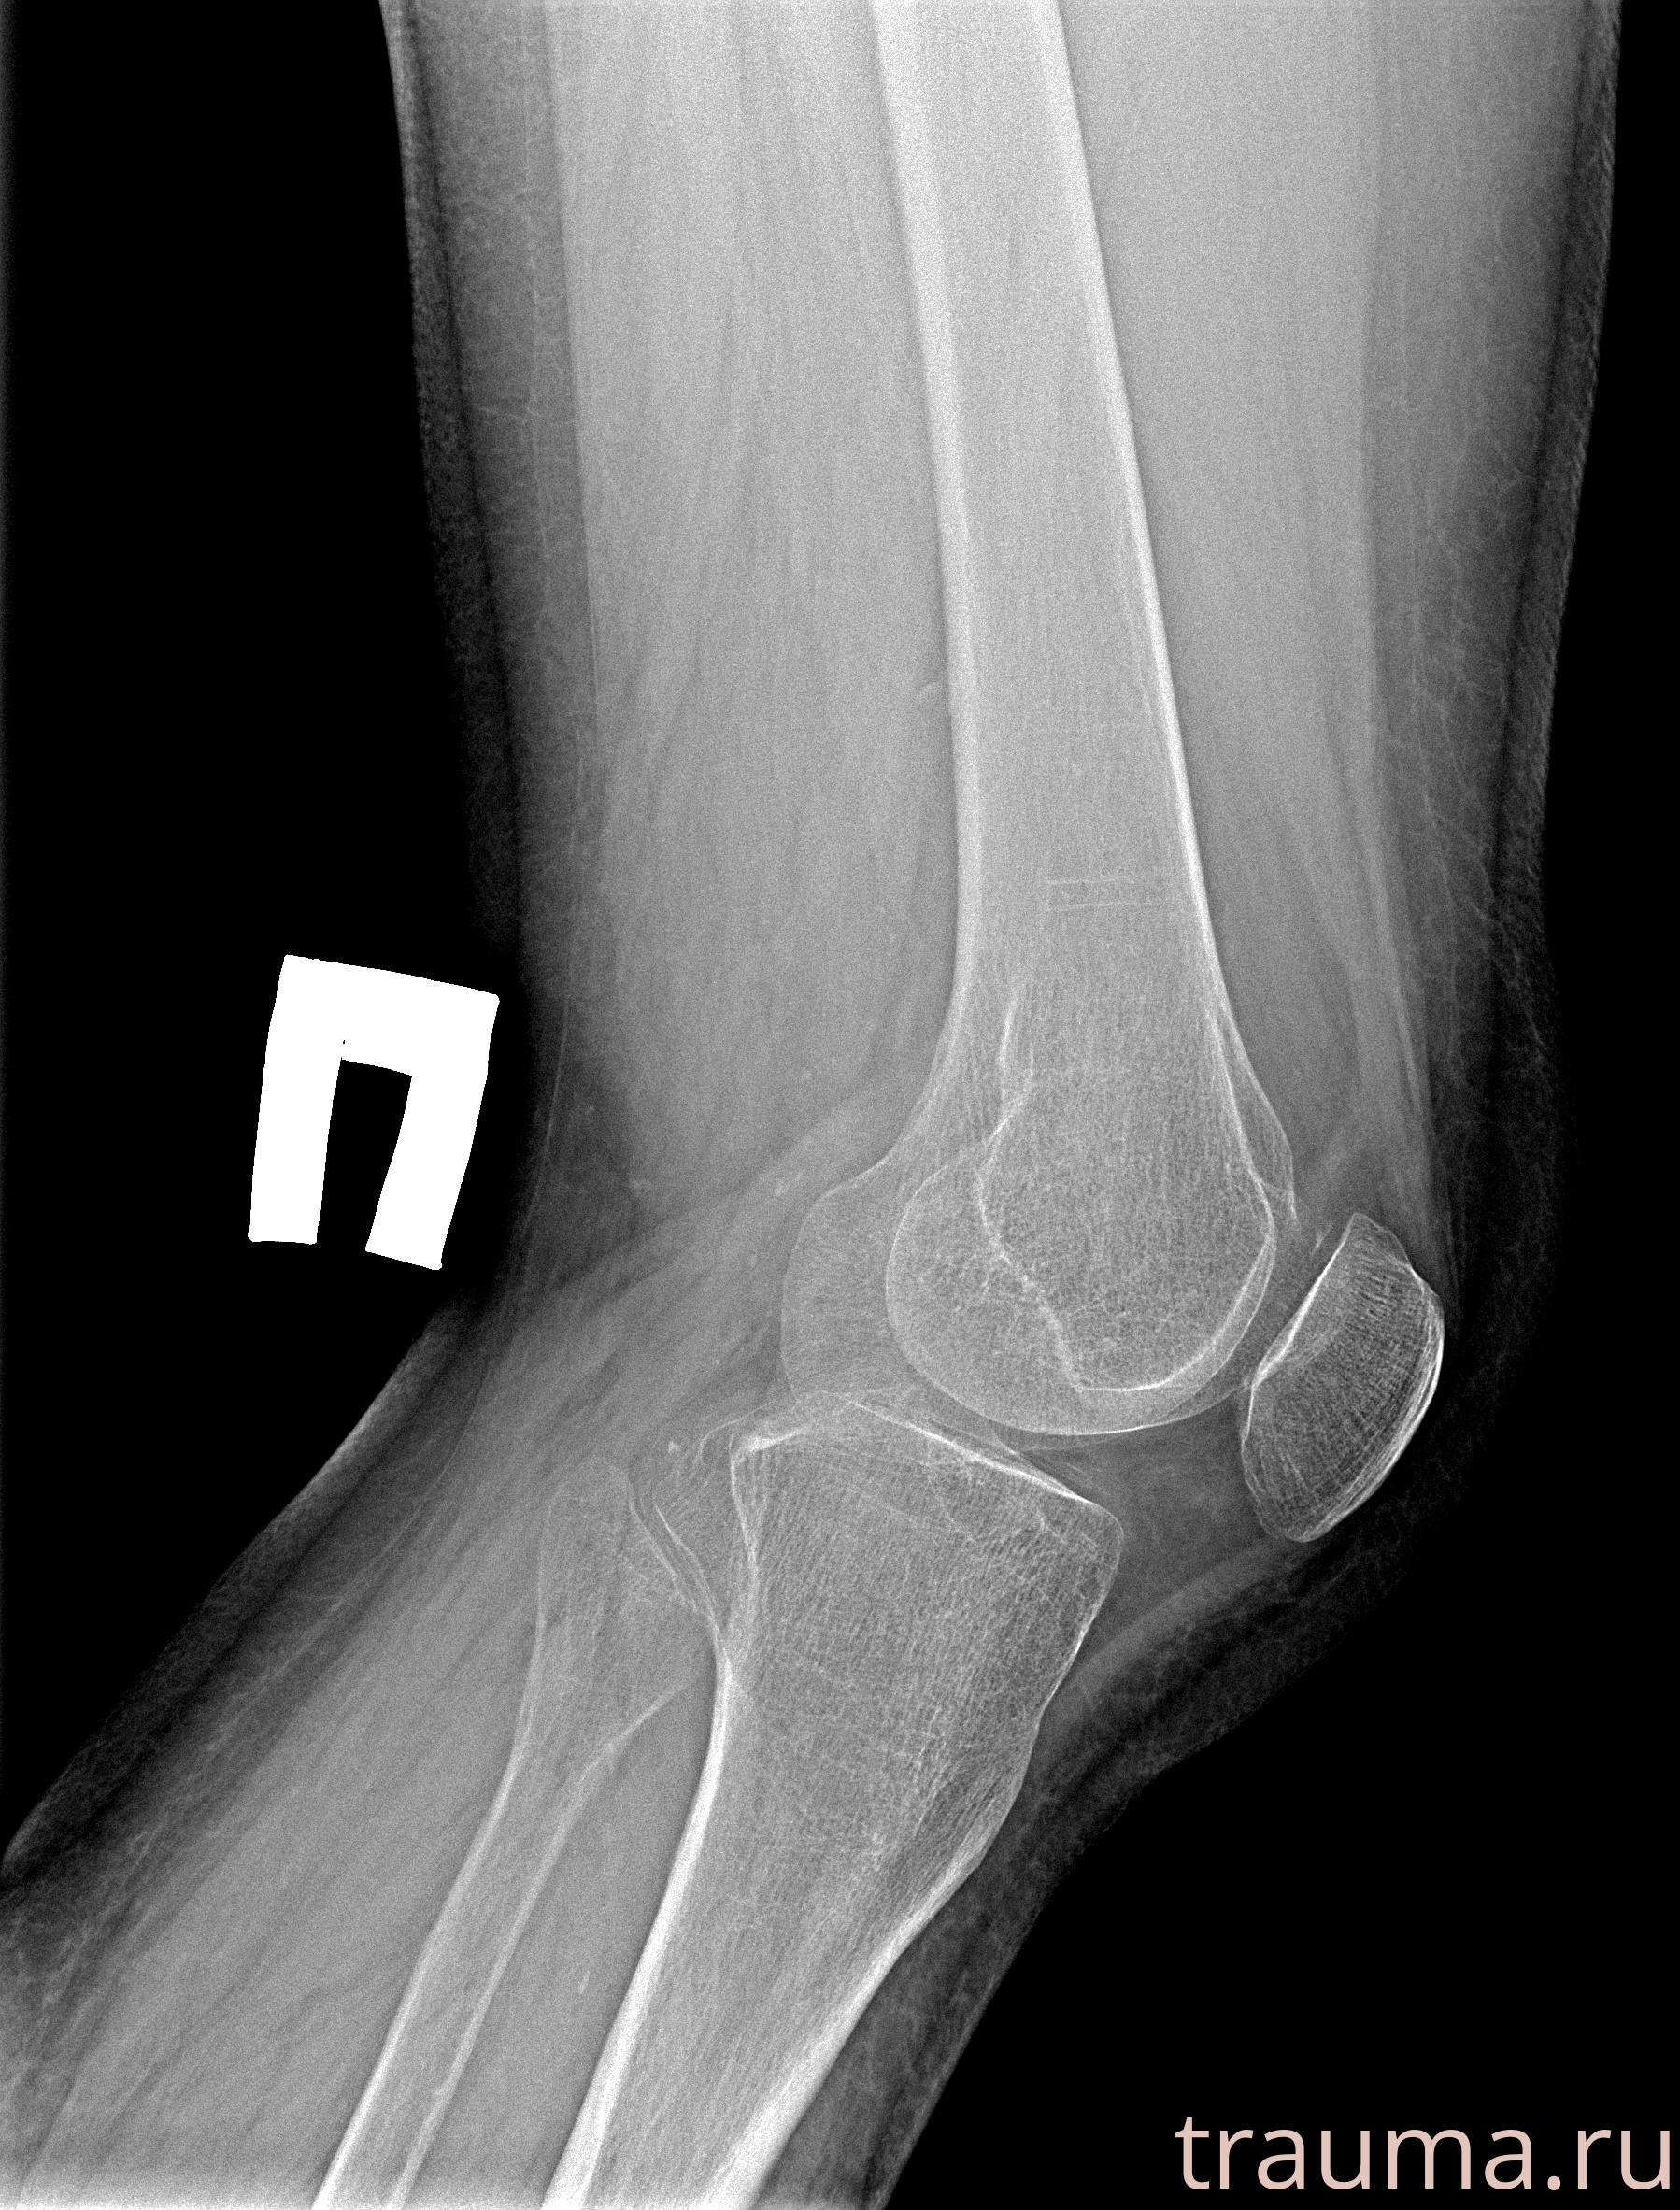

Рентгенограммы

Рентген на дому: по вашему адресу приезжает врач-рентгенолог, травматолог-ортопед с мобильным рентгеновским аппаратом, проводит диагностику травмы или заболевания, делает необходимые рентгенограммы, дает рекомендации по дальнейшему лечению. Получить качественные снимки в домашних условиях возможно благодаря уникальной методике, разработанной МосРентген Центром для института  Склифосовского